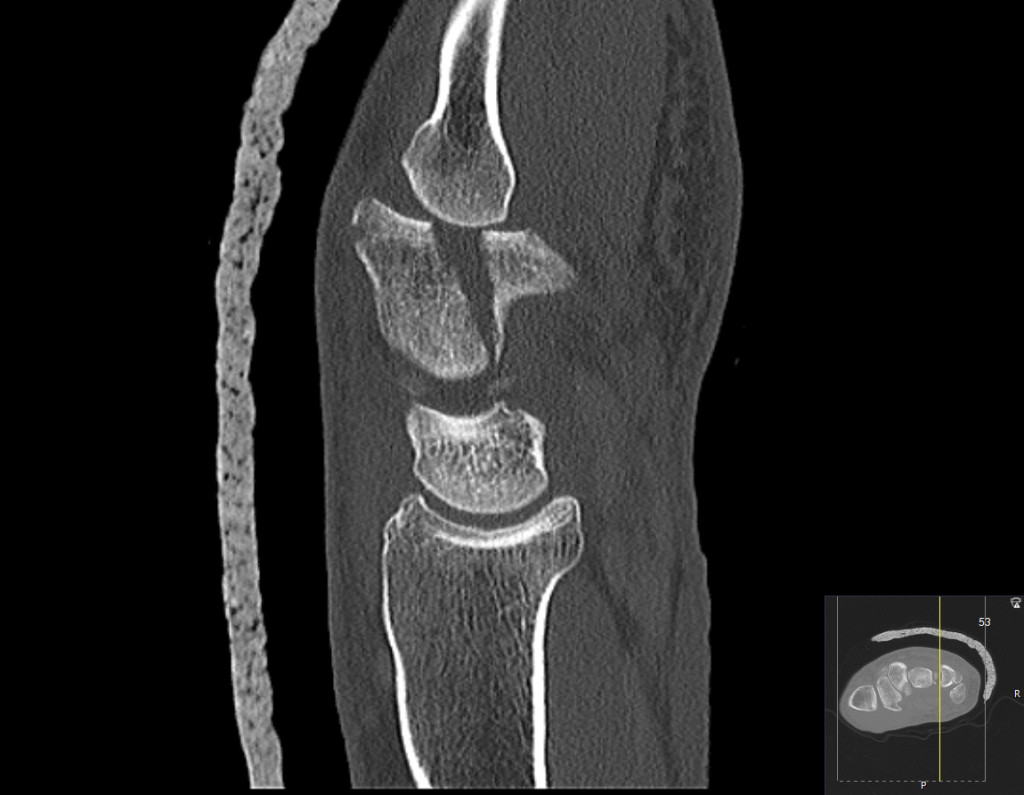

The image shows a longitudinal fracture in the body of the hamate with subluxation of the fifth carpometacarpal joint in a man in his forties after a fall.

Hamate fractures are rare, accounting for about 2–4 % of all carpal fractures (1). Diagnosis and treatment are often delayed because clinical findings are limited and the fracture may be difficult to detect on conventional X-ray images. CT is therefore recommended in the case of continued pain in the ulnar region of the wrist following a negative X-ray (1, 2). Fractures are divided into fractures of the body and of the hook. Injuries are caused by axial compression of the hamate bone through the fourth and fifth metacarpals, both of which articulate with the hamate bone. This can result in subluxation of carpometacarpal joints four and five, with a coronal fracture line through the hamate bone, most commonly the dorsal part. The fourth and fifth carpometacarpal joints allow about 30o of motion, and are important for grip strength. Healing without step formation and without subluxation of the carpometacarpal joint is therefore important to reduce the risk of osteoarthritis. Isolated, non-displaced fractures of the body are usually considered to be stable and can be treated by cast immobilisation, while it is recommended that displaced fractures be reduced and fixed with pins, or alternatively with plates or screws, with simultaneous reduction and fixation of the subluxated carpometacarpal joint.

Given appropriate treatment, the prognosis is good. The most common long-term consequence is pain with heavy strain (2), which may be due to the development of osteoarthritis, which is always a risk after an intra-articular fracture. This patient first underwent a closed reduction and pin fixation procedure. The fracture healed, but the patient developed post-traumatic osteoarthritis in both the fourth and the fifth carpometacarpal joints, and one year after the injury underwent a procedure to stiffen the fourth and fifth carpometacarpal joints with plate fixation.